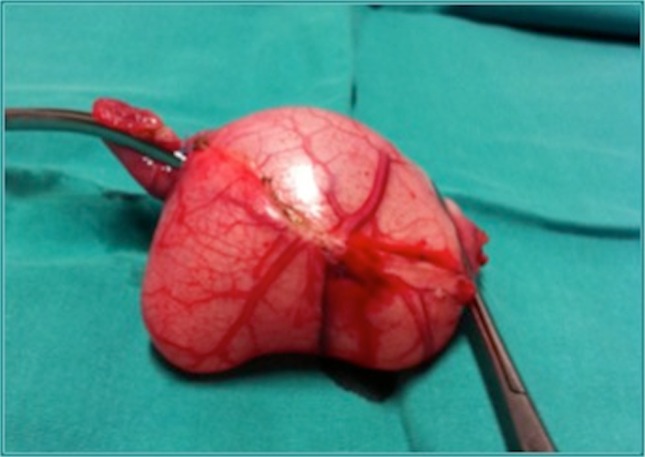

Fig. 2.

The surgical specimen shows the enteric duplication cyst